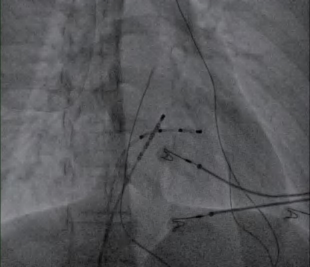

(2)常规选择股静脉穿刺两次或三次,分别置入四极标测电极导管至右心室(图2-2-1)、十极标测电极导管至冠状窦(图2-2-2),必要时再放置四极标测电极导管至希氏束;或者先穿刺一侧股静脉,再穿刺一侧颈静脉或锁骨下静脉作为放置标测电极的入路。

图2-2-2 电极导管置入冠状窦